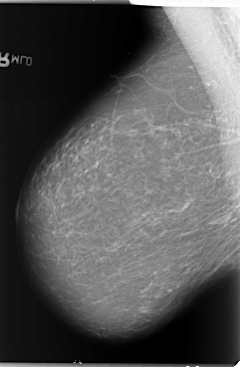

B_3105_1.LEFT_CC

LEFT_CC LINES 5888 PIXELS_PER_LINE 3656 BITS_PER_PIXEL 12 RESOLUTION 50 OVERLAY

FILE: B_3105_1.LEFT_CC.OVERLAY

TOTAL_ABNORMALITIES 1

ABNORMALITY 1

LESION_TYPE CALCIFICATION TYPE PLEOMORPHIC DISTRIBUTION CLUSTERED

LESION_TYPE MASS SHAPE IRREGULAR MARGINS ILL_DEFINED

ASSESSMENT 4

SUBTLETY 3

PATHOLOGY BENIGN

TOTAL_OUTLINES 1

BOUNDARY